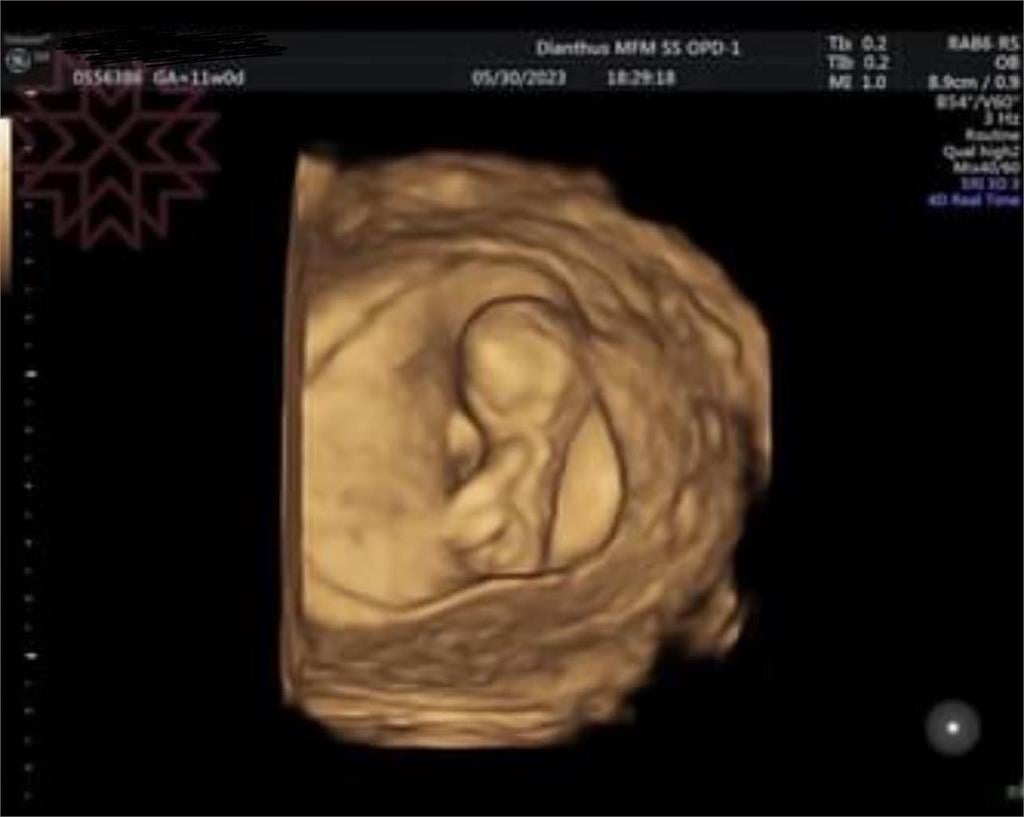

楊繡惠昨日突然在臉書發文,她還開心地說,「哈哈恭喜我吧!滿3個月再公開」。她也曝光了2張超音波照片,看起來似乎是寶寶的超音波照,讓大批網友都相當驚喜,懷疑是不是楊繡惠懷孕了,不少人也在底下留言恭喜,「恭喜姐啊」、「阿姊…恭喜…我雖然覺得怪怪的…但我沒證據」、「恭喜,期待~」。

後續有眼尖網友揪出1細節,發現這2張超音波的左上角有標示出孕媽咪的資訊,似乎是1名1992年出生的柯姓女子懷孕,「左上方有準媽媽的名字!」、「名字露餡了」、「左上角名字不是你的餒」、「超音波照片有媽媽的名字啦!媽媽應該是1992年的」。後來楊繡惠也將孕婦的資訊打馬賽克,但還是沒有說明超音波照片的真相為何。